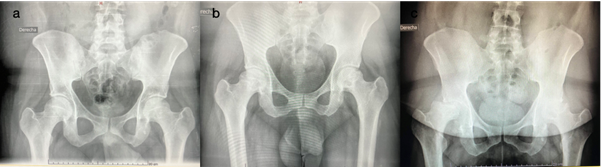

Las radiografías de pelvis 2015 no muestran alteraciones en la morfoestructura ósea. En 2016 aparecen imágenes radiolúcidas rodeadas de áreas escleróticas epifisarias bilaterales, con perdida de la esfericidad normal de la cadera derecha, por último en 2017 se observan ambas caderas afectadas, predominando el hundimiento epifisario, el colapso y alteración de la esfericidad de la cabeza femoral así como la pérdida de la luz articular. Figura 1.

Se puede ver la rápida evolución de la enfermedad en la cabeza femoral, pasando de un estadio I de la clasificaciones Ficat y Arlet en 2015, a un estadio II/III en 2016 y finalizar en el estadio IV en 2017. Tabla 1.

En las radiografías de ambas rodillas se destaca alteración de la estructura ósea donde se evidencian zonas de mayor radiolucidez a nivel de ambas epífisis femorales rodeadas de zonas escleróticas. Tanto a nivel del codo derecho como del cuello de pie izquierdo las radiografías obtenidas no mostraban alteraciones.